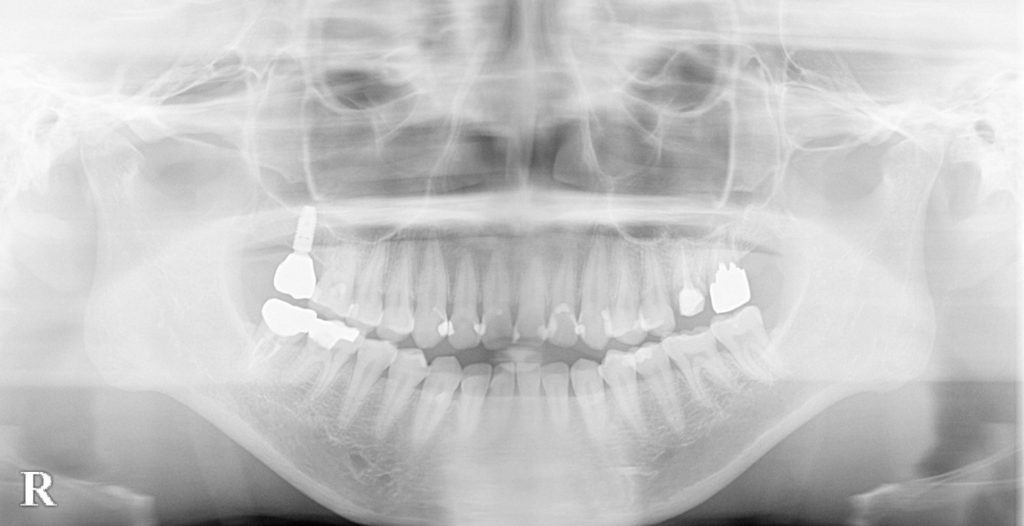

妊娠中の嘔吐習慣によるエロージョン(酸蝕症)と歯軸傾斜を短期間で改善した症例(インハウスアライナー、セラミック、デジタル)

| 診断名 | 前歯部審美障害(酸蝕および咬耗による歯牙形態異常)および発音障害 |

| 年齢・性別 | 39歳 女性 |

| 治療方法 | デジタルセットアップ→診断→院内製作マウスピース型矯正装置による矯正治療→前歯部補綴 |